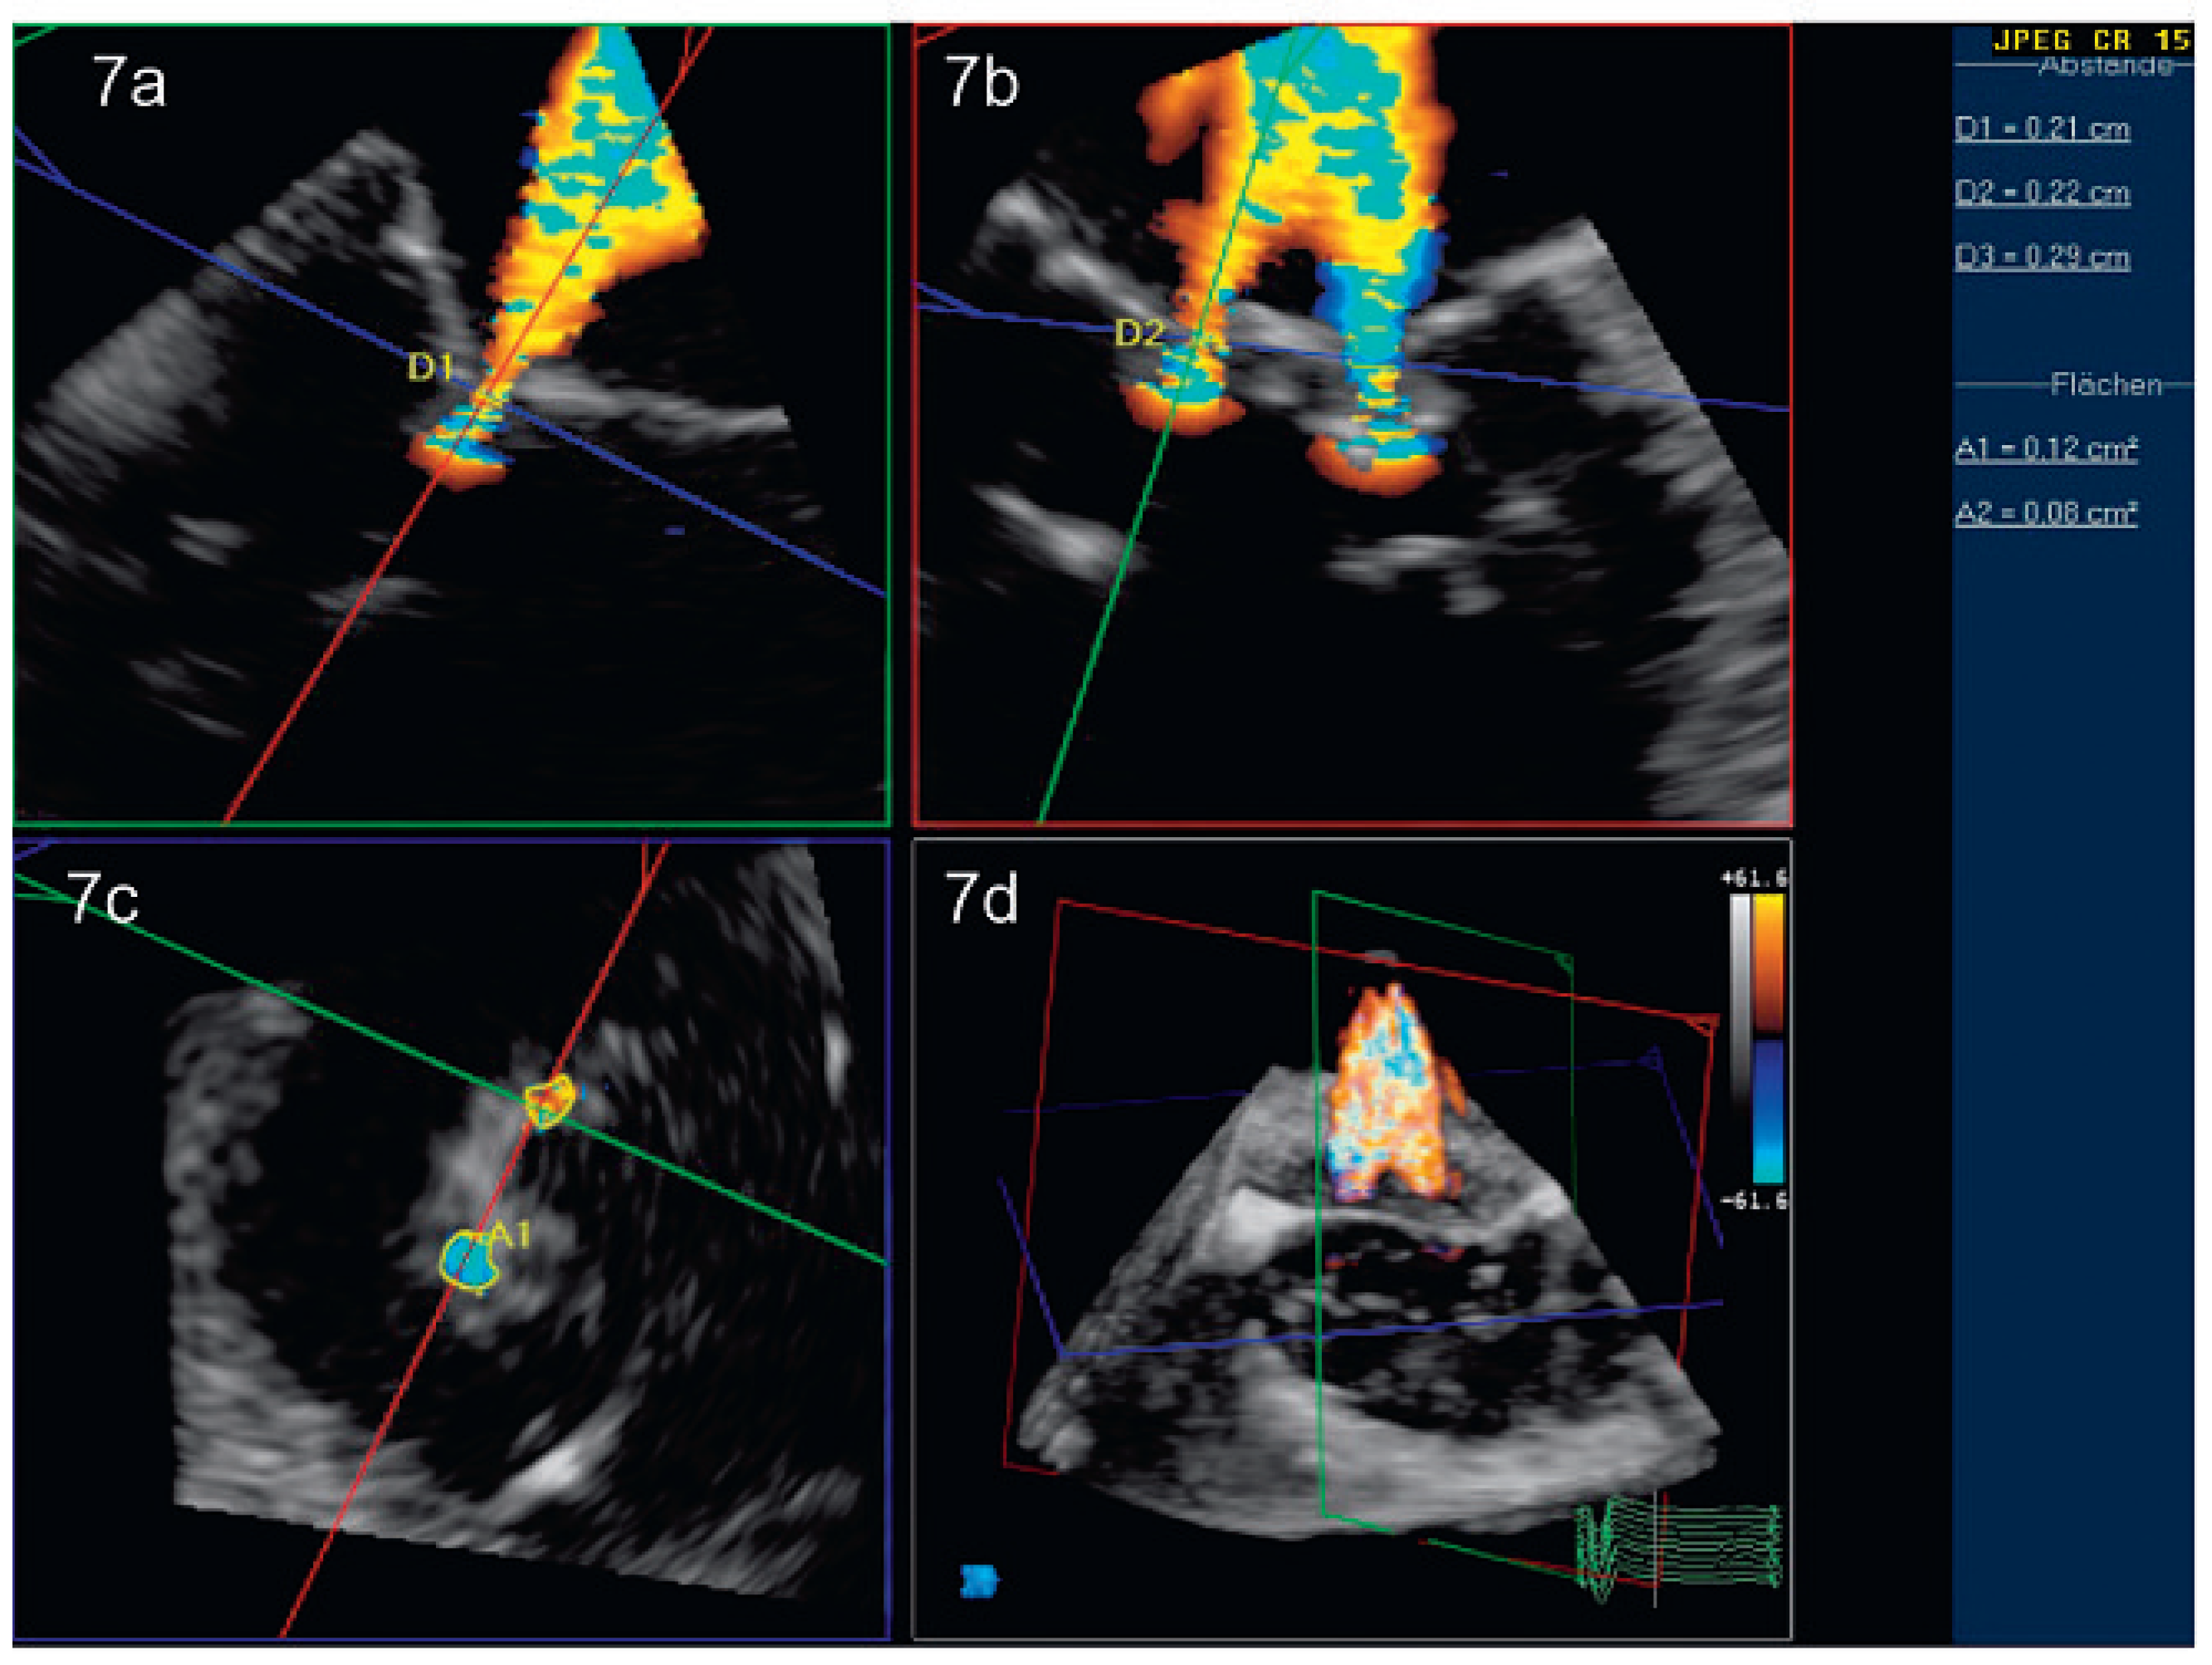

Peri- und postinterventionelle Beurteilung der Mitralklappe